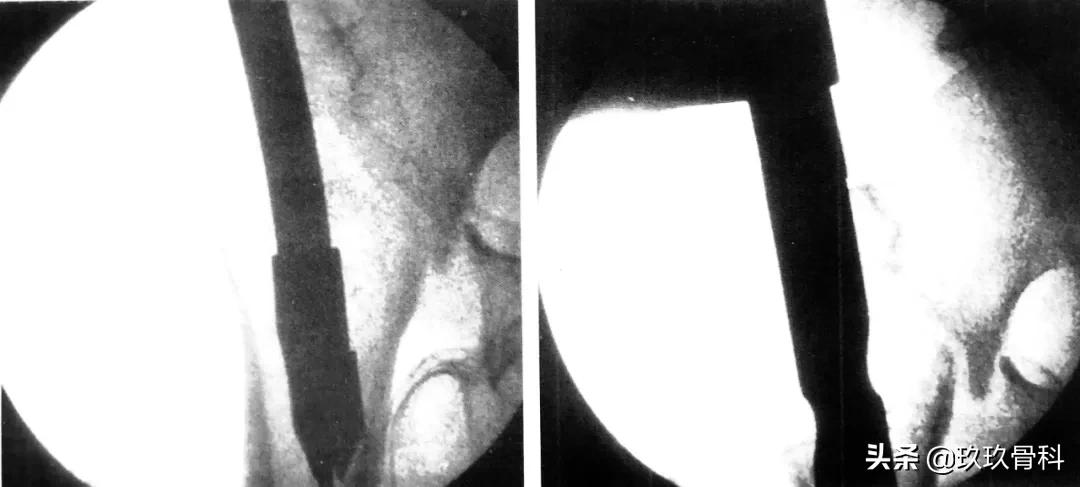

肱骨逆行髓内钉,左图为入钉口置备,右图为穿入多根弹性髓内钉